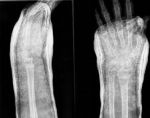

Ezen betegek azonban évekkel később egy másik problémával szembesülnek, ugyanis gyakran alakul ki náluk olyan fokú csontritkulás, mely többszörös töréshez is vezethet.

A Koreai Rákkutató Központi Kórház munkatársai vizsgálataik során megállapították, hogy a gyomorrákos daganat műtéti eltávolítása után a betegek 38,3 százalékánál csontritkulás, 46,6 százaléknál csigolyadeformitás alakult ki, 45,9 százalékuk pedig csont eredetű fájdalomról panaszkodott.